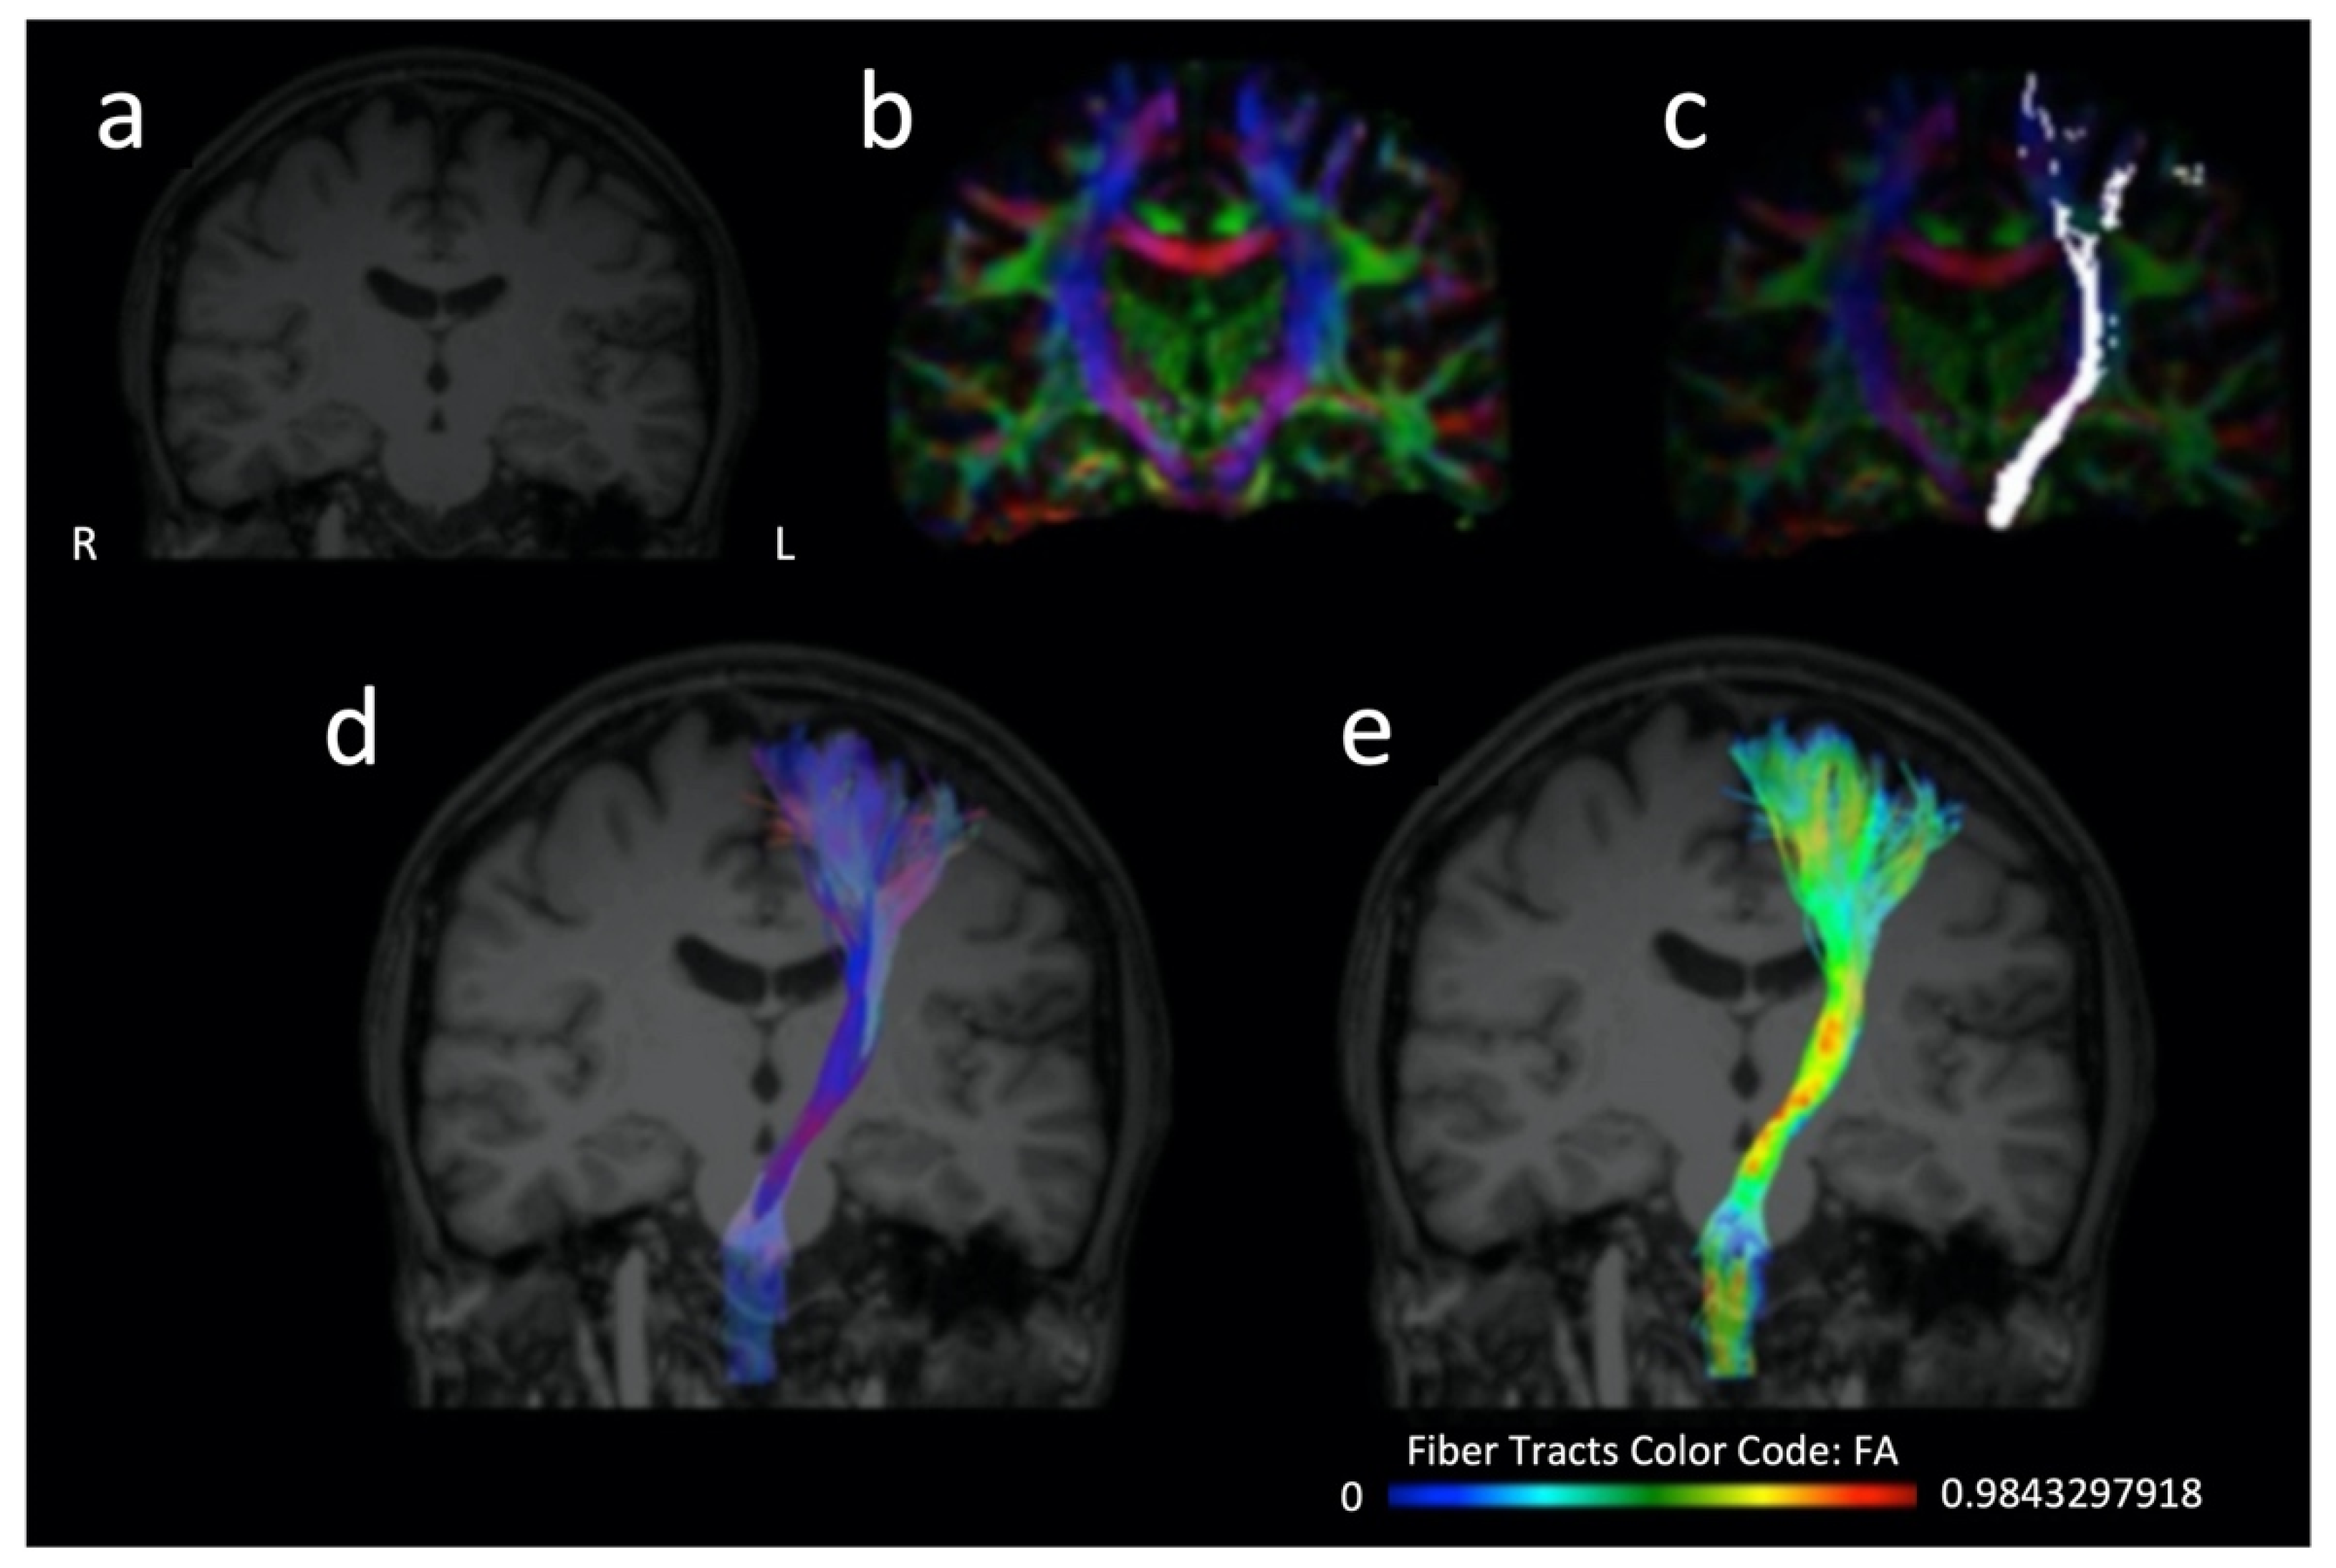

The majority of studies assessing DTI value as a stroke recovery biomarker have focused primarily on corticospinal tract (CST) integrity [6]. CST is a descending pathway (Figure 2) of great significance for motor function. Thus, it is reasonable that research on post-stroke rehabilitation has vastly focused on its assessment [10,11]. Among DTI parameters, FA is the most frequently utilized in research related to stroke recovery. Decrease of FA values of CST within the subacute stroke phase is widely associated with poorer motor outcomes [6,12,13]. Nevertheless, both increased and decreased FA values can be seen acutely [14]. Interestingly, it has been suggested that FA increase in the acute phase can be probably attributed to the more profound decrement in isotropic compared to anisotropic diffusion; therefore it cannot predict lesion age at the hyperacute stage [14]. Methods of FA of CST evaluation include measuring FA remotely at the stroke location, or the number of fibers passing through the stroke with tractography and calculating the ratio between the ipsilesional and contralesional pyramidal tracts [12]. Besides CST, DTI research has also expanded to other WM tracts, depending on the type of neurological deficit explored [15], including for example the common language-related WM network not only in the left but also in the right hemisphere [16,17,18,19,20].

Figure 2.

Three-dimensional T1 sequence (a), color fractional anisotropy map (b), distribution of the corticospinal tract fibers projected over a color fractional anisotropy map (c), three dimensional representation of the corticospinal tract (d,e) which is further color-coded according to the distribution of the fractional anisotropy values along the tract (e) and projected over a T1 sequence (d,e). The reconstruction of the corticospinal tract has been performed on a healthy subject (who provided written informed consent for the data acquisition, analysis and presentation) using the Brainance MD platform (Advantis Medical Imaging).